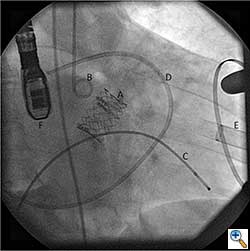

After valve implantation, it is critical to confirm valve competence, visualize coronary flow, and check for aortic injury by performing echocardiography and completion angiography (Figure 3). In the stabilized patient, the large femoral sheath is removed while maintaining wire access, ensuring no damage to the iliac artery. Once flow is confirmed in the proximal and distal femoral artery, the guidewire can be removed. The artery is clamped on either side and the arteriotomy is closed primarily with interrupted 5-0 or 6-0 prolene. The incision site is closed in standard fashion with absorbable suture in layers. The femoral arterial and venous sheaths in the contralateral groin may be left in place and then removed when the activated clotting time reverses to normal. Patient is taken back to the cardiothoracic intensive care unit for postoperative recovery.